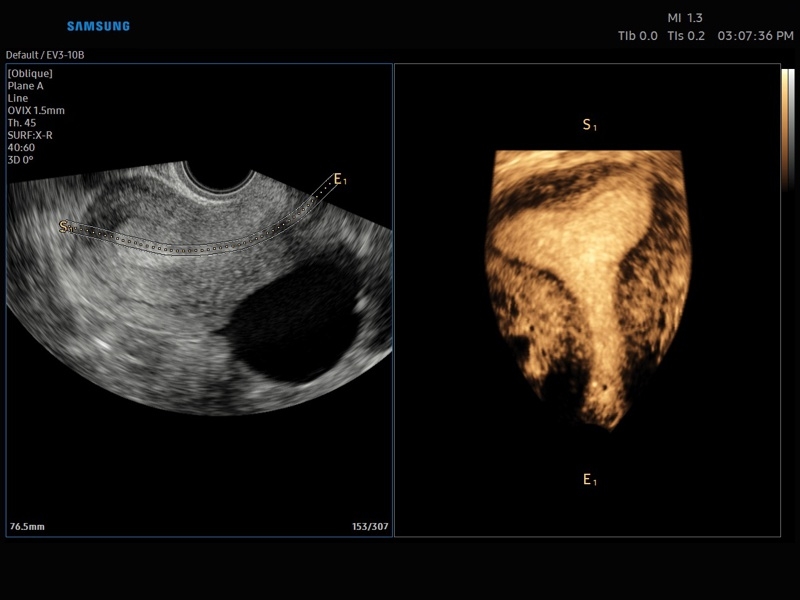

• Модуль Realistic Vue - программа реконструкции реалистичного 3D УЗИ, при котором на объемное изображение накладывается виртуальный источник освещения. Специальный процессинговый алгоритм воспроизводит трехмерную анатомию плода с исключительной детализацией.

• МодульCrystal Vue- программа реконструкции прозрачного 3D УЗИ, которое получается при одновременном усилении внутренних и наружных структур. Применяется для визуальной оценки состояния плода и матки, помогает лучше идентифицировать мягкие ткани и кости.

• Модуль Crystal Vue Flow- программа реконструкции прозрачного 3D УЗИ, которое получается при одновременном усилении внутренних и наружных структур. Применяется для визуальной оценки состояния плода и матки, помогает лучше идентифицировать мягкие ткани и кости. Так же визуализирует объемный кровоток.

• OVIX(Oblique View eXtended) - получение фрагмента трехмерного изображения (в виде нескольких полупрозрачных сканов, последовательно наложенных один на другой) в направлении произвольного косого среза трехмерного объекта исследования.